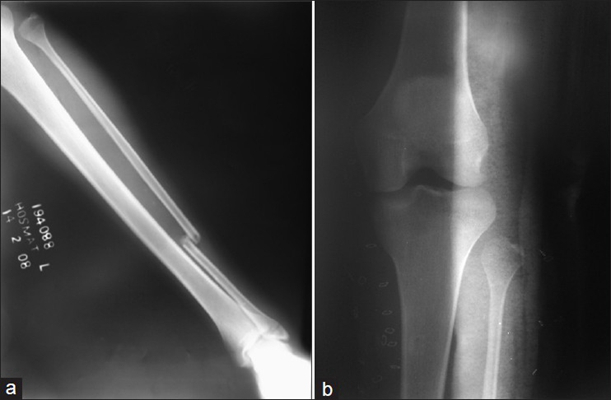

骨折圖片